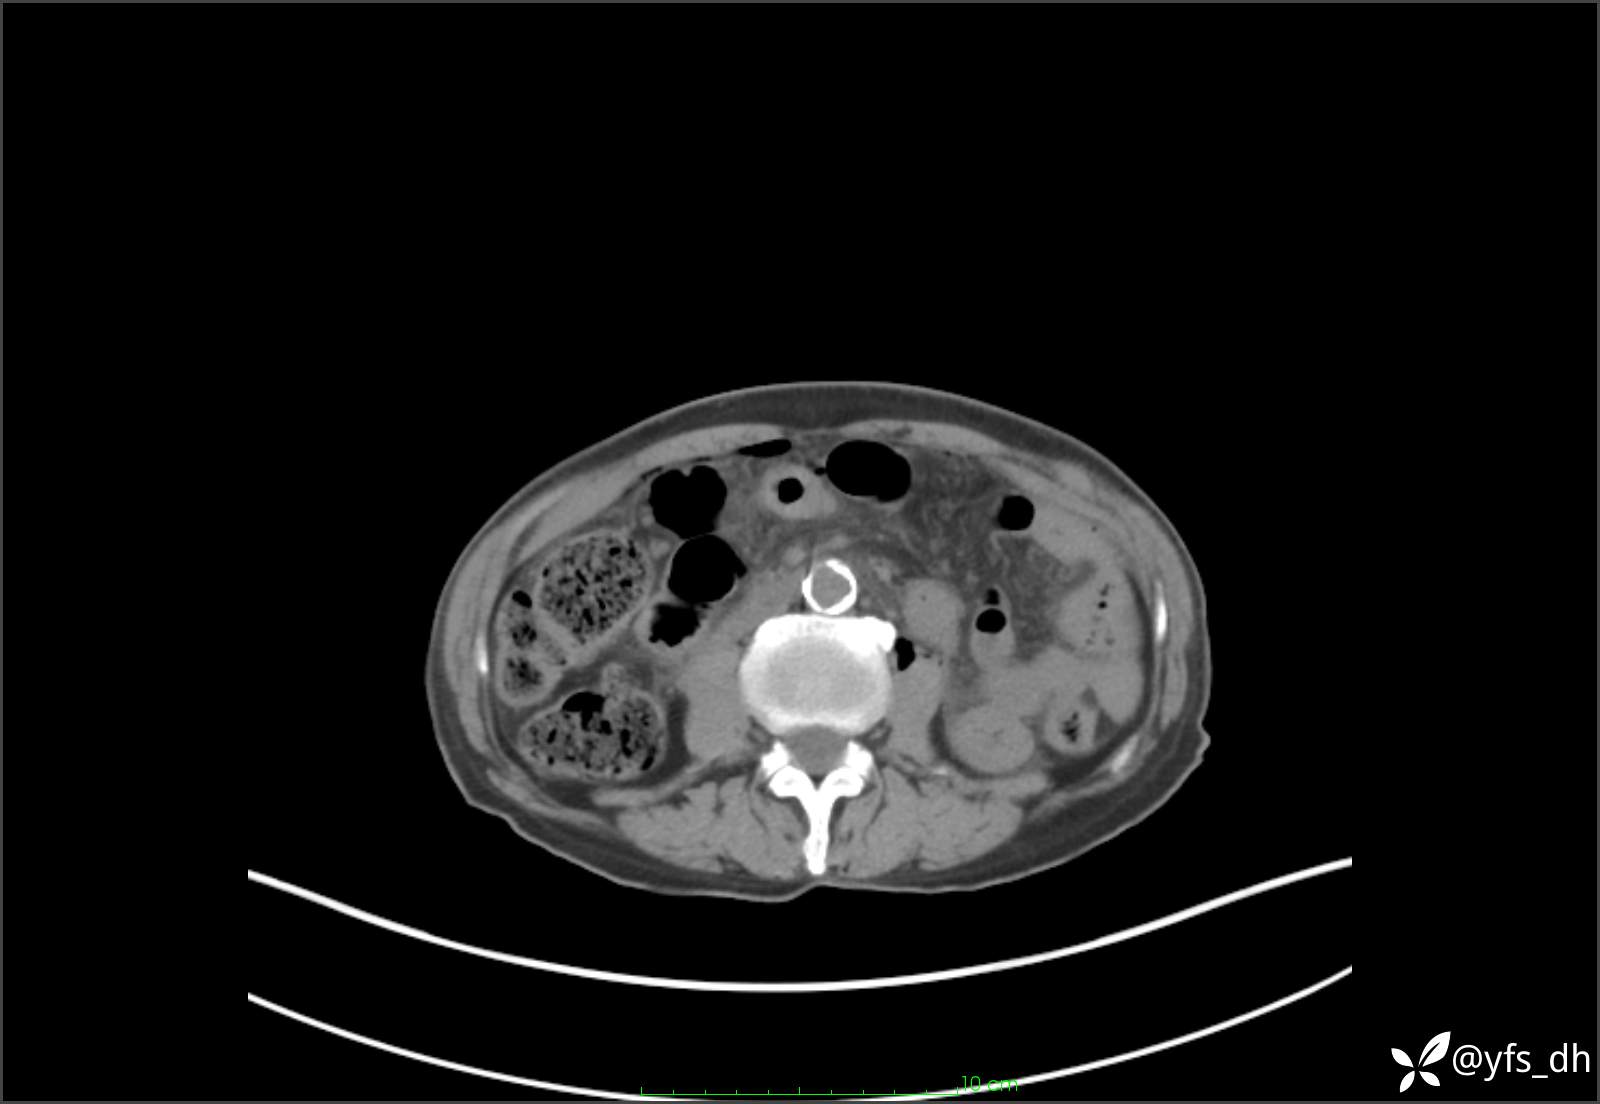

1.简要病史:患者4天前突发上腹部疼痛不适,但可以忍受。3小时前饭后突然加重,不能忍受后就诊。

2.简要手术记录:术中见腹盆腔大量肠液及粪便,乙状结肠中下段见一约3cm的破口。